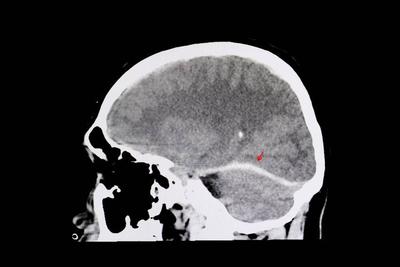

2、进行头颅ct的检查,这种检查速度快,对于脑血管病变诊断是比较明确的,如果出现了脑供血不足,ct内就可以看见颅内的缺血软化灶。